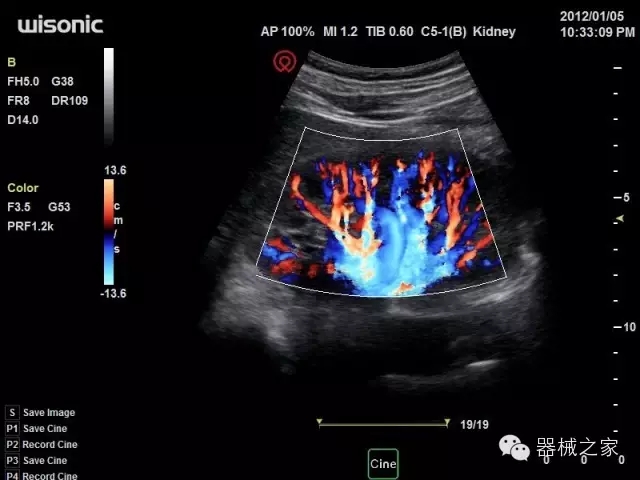

經(jīng)典產(chǎn)品:四葉草

臨床圖片賞析

產(chǎn)品特點

·全球目前唯一一款配備主機雙探頭接口,整機重量(含電池)在5公斤以內(nèi)的便攜式彩超;

·一款互聯(lián)網(wǎng)彩超,只要有手機信號的地方就可以非常方便地實現(xiàn)遠程會診和病案調??;

·獨有的HoloTM PW 實時3取樣門PW成像技術,精確進行血管診斷;

·一鍵優(yōu)化B、Color、PW,Auto Doppler自動識別血管位置、偏轉角度等,提高工作效率;

·30°超廣角精細偏轉成像技術,更優(yōu)異的頻譜圖像;